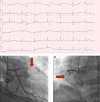

Cardiogenic Shock

Keywords: acute coronary syndrome; cardiogenic shock; revascularization; shock.